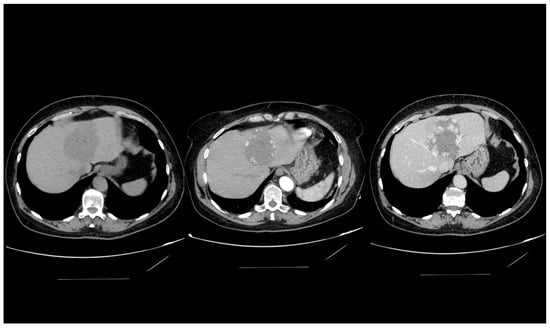

4.4. Computed Tomography

6.1. Giant Haemangioma